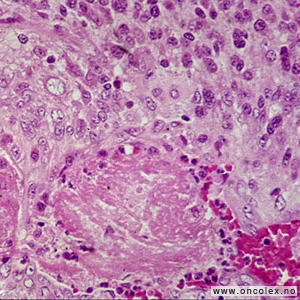

Analyse av celle- og vevsprøver

Celle- og vevsprøver sendes til cytologisk eller histologisk analyse. I tillegg til at man studerer cellene i mikroskopet, gjør man avanserte immunhistokjemiske og genetiske analyser. Nøyaktig hvilke analyser som gjøres er avhengig av hvilken type svulst man mistenker at pasienten har.